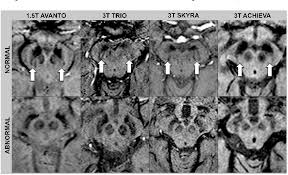

Lewy, the scientist who discovered them. Loss of substantia nigra hyperintensity on 7 tesla mri of parkinson's disease, multiple system atrophy, and progressive supranuclear palsy. Besides nuclear imaging methods, the clinical utility of structural neuroimaging with magnetic resonance imaging (mri) for differential comparison between dementia with lewy bodies and alzheimer's disease. You also might see things that aren't there, called hallucinations. Lbd is a term that covers two conditions that have similar. Protein deposits, called lewy bodies, develop in nerve cells in the brain regions involved in thinking, memory and movement (motor control). Certain nuclear scans of the brain, including positron emission. How is lewy body dementia (ldb) diagnosed? Dr michael firbank discusses his study using functional mri in lewy body dementia and alzheimer's disease at the newcastle university institute. Focal atrophy in dementia with lewy bodies on mri: Memory loss is not always an early symptom. Lewy body dementia (lbd) is a type of progressive dementia. Many people also experience changes in alertness including daytime sleepiness, confusion or staring spells.

Differences In Mr Features Of The Substantia Innominata Between Dementia With Lewy Bodies And Alzheimer S Disease Semantic Scholar

Differences In Mr Features Of The Substantia Innominata Between Dementia With Lewy Bodies And Alzheimer S Disease Semantic Scholar from d3i71xaburhd42.cloudfront.net